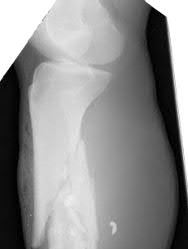

Illustration A shows a heterotrophic non-union of the tibia after intramedullary nailing. The patient was treated with exchange nailing with a larger nail. On the right shows a 4 month post-op radiograph after exchange nailing showing osseous union at the fracture site.

Reamed exchange nailing is recommended for the management of aseptic nonunions of noncomminuted tibial shaft fractures. Union rates have been reported between 76-96% in large studies.

Tibial exchange nailing promotes osseous bone healing of non-unions by providing biological and mechanical support. The biological support is provided by reaming the medullary canal. This increases periosteal blood flow and stimulates periosteal new-bone formation. The mechanical support is provided by a larger-diameter intramedullary nail, which increases the rigidity and strength of the nail.

Brinker et al. reviewed the concept of exchange nailing of nonunited long bone fractures. They showed that exchange nailing is the most successful in the treatment of nonunions following closed or open fractures without substantial bone loss. Aseptic, noncomminuted diaphyseal femoral and tibial shaft fractures showed the highest rates of union with exchange nailing, which were found to be 76-100% and 72-96%, respectively.